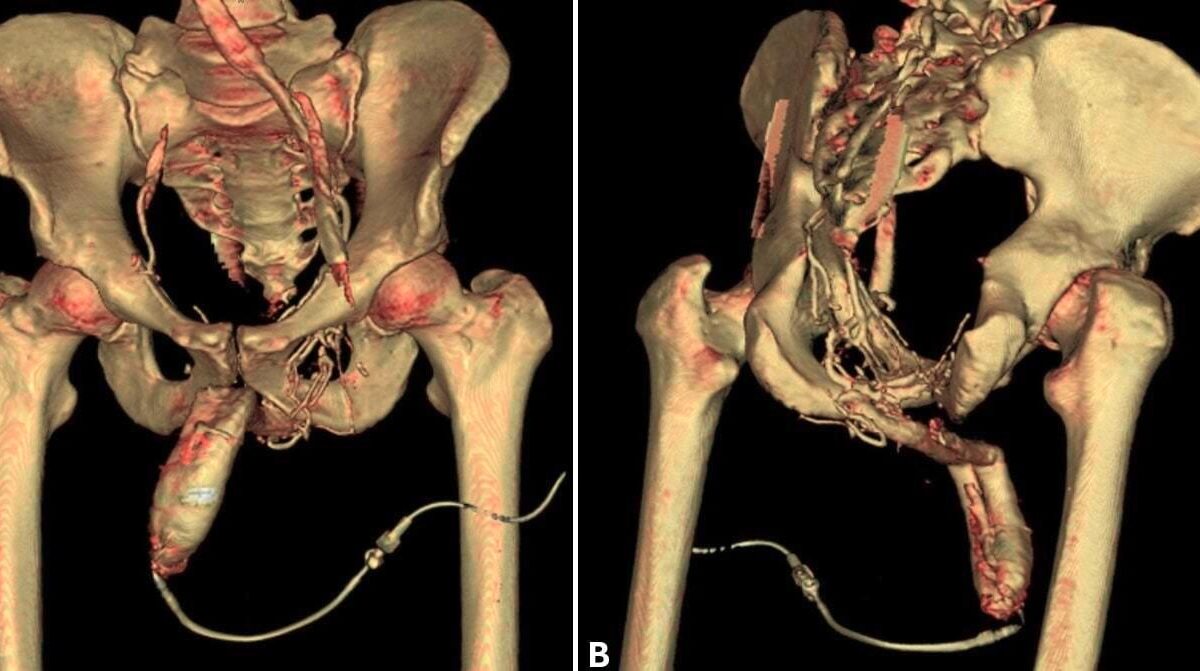

La radiologie interventionnelle redéfinit la prise en charge des traumatismes chez les sportifs de haut niveau. Des nouvelles procédures offrent des solutions thérapeutiques qui réduisent la morbidité, épargnent les tissus mous et autorisent un retour à l’entraînement ...